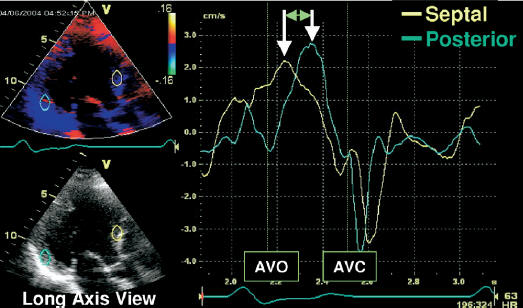

Intra-LV Delay: Color Tissue Doppler Method

Among all methods, this is the preferred

method.

- Obtain color tissue Doppler curves in apical views (A4C, A2C and A3C)

during a breath hold.

- Measure the opposing wall

delay using the

peak-to-peak time distance between S waves:

: A4C - inferior septum to lateral wall

: A2C - anterior wall to inferior wall

: A3C - anterior wall to inferolateral (posterior) wall.

- Report the largest opposing wall delay.

: Abnormal opposing wall delay by

color tissue Doppler >65 msec.